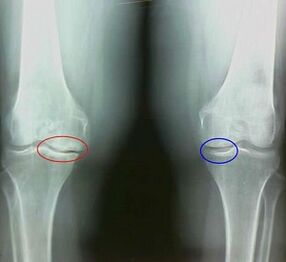

Artroz, eklemin kıkırdak dokusunun yok edilmesiyle ilişkili dejeneratif distrofik bir işlemdir. Kıkırdak yavaş yavaş yok edilir, kuru, eklemin kemikleri arasındaki mesafe azalır, bu da ağrının nedenidir. Şiddetli formlarda yıkım kemikleri etkiler. Daha gözenekli olurlar, yoğunluklarını kaybederler, kırılgan olurlar.

Eklem şişer, kalıcı bir ağrı sendromu gelişir ve hareket sırasında yoğunlaşır. Arthroz ile ağrı sadece fiziksel aktiviteden sonra meydana gelir, karakteristik bir krizi duyabilirsiniz veya eklemde tıklamalar, yavaş yavaş eklem deforme olur ve hareketliliği kaybeder.

Kıkırdak ve kemik dokusunun yenilgisi sadece ihmal edilen bir durumda geç aşamalarda meydana gelir. Artroz ile, kıkırdak dokusu önce etkilenir ve daha sonra kemik, sinovyal membranın iltihabı ikincil kökenlidir, yani arka planlarına karşı gelişir.

Artroz yavaş yavaş gelişir ve erken aşamalarda fark edilmez. Genellikle fiziksel yorgunluk için alınır. Kronik artroz formuna osteoartroz denir. Neyin daha kötü olduğu sorusuna - artroz veya osteoartroz, cevap açıktır. Son seçenek, artrozun gelişiminin ve akut formunun bir sonucudur.

Artroz belirtileri arasında aşağıdakiler ayırt edilir:

- Acılar, fiziksel aktiviteden sonra, ani hareketler, dönüşler, eğimler, dinlendikten sonra ağrı geçer;

- Eklemlerde karakteristik bir kriz not edilir;

- Hareketlilikten 15-20 dakika içinde geçen uzun süreli dinlenme sonrası ağrı (bu, eklemde meydana gelen durgun fenomenlerle ilişkilidir);

- Venöz durgunluk nedeniyle ortaya çıkan gece donuk ağrıyan ağrı hakkında endişelenmek;

- Enflamatuar patoloji biçimine ödem ve ağrı eşlik eder;

- Eklem deforme olur, hareketliliği azalır.